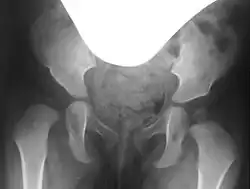

In hip dysplasia, the femoral head lacks sufficient lateral and anterior coverage, known as the acetabular rim. This inadequate coverage can cause the femoral head to slip upward and, depending on the severity, may lead to dislocation of the hip.[3]

Lateral coverage is measured using the acetabular angle (AC angle) on a pelvic X-ray, defined as the angle between a horizontal line through the Y-sutures and a line along the acetabular rim. In healthy newborns, the AC angle is approximately 25°, decreasing to about 15° by age 6 and 11–12° by age 12.[6] Acetabuloplasty aims to correct the AC angle to these physiological values, achieving an anatomical reconstruction.[6]